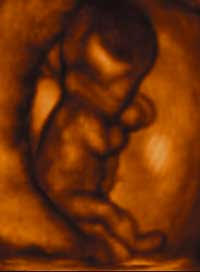

Dr. McCarthy de Mere, medical doctor and law professor of the University of Tennessee, testified: “The exact moment of the beginning of personhood and of the human body is at the moment of conception.”

Abortion Rights Action League, Dr. Bernard Nathanson, said “It is atrocious for anyone now to maintain that a fetus [unborn child] is simply a lump of meat, or something insignificant or an unprotectable life.”

In 1933, abortion advocate and former medical director of the Planned Parenthood Federation of America, Dr. Alan Guttmacher, wrote, “We of today know that man is born of sexual union… and that the embryo is formed from the fusion of two single cells, the ovum and the sperm. This all seems so simple and evident to us that it is difficult to picture a time when it was not part of the common knowledge.” And in 1961 Dr. Guttmacher wrote, “Fertilization, then has taken place; a baby has been conceived.” If a man who has dedicated his life to promotiong contraception and abortion can acknowledge the scientific facts of when life begins, why can’t we?